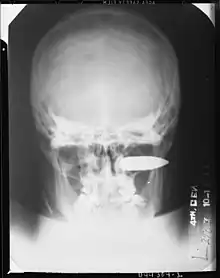

Exemple de traumatisme grave : Blessure de guerre au visage, par balle de mitrailleuse (calibre 0,5), entrée juste au-dessous du sourcil droit. 11 jours après la blessure, le patient a commencé une hémorragie si abondante qu'il a été impossible de mener à bien les procédures d'urgence. Ce patient est alors décédé (seconde guerre mondiale, archives, 4e Hôpital general de l'armée américaine)

(archives militaires médicales américaines)